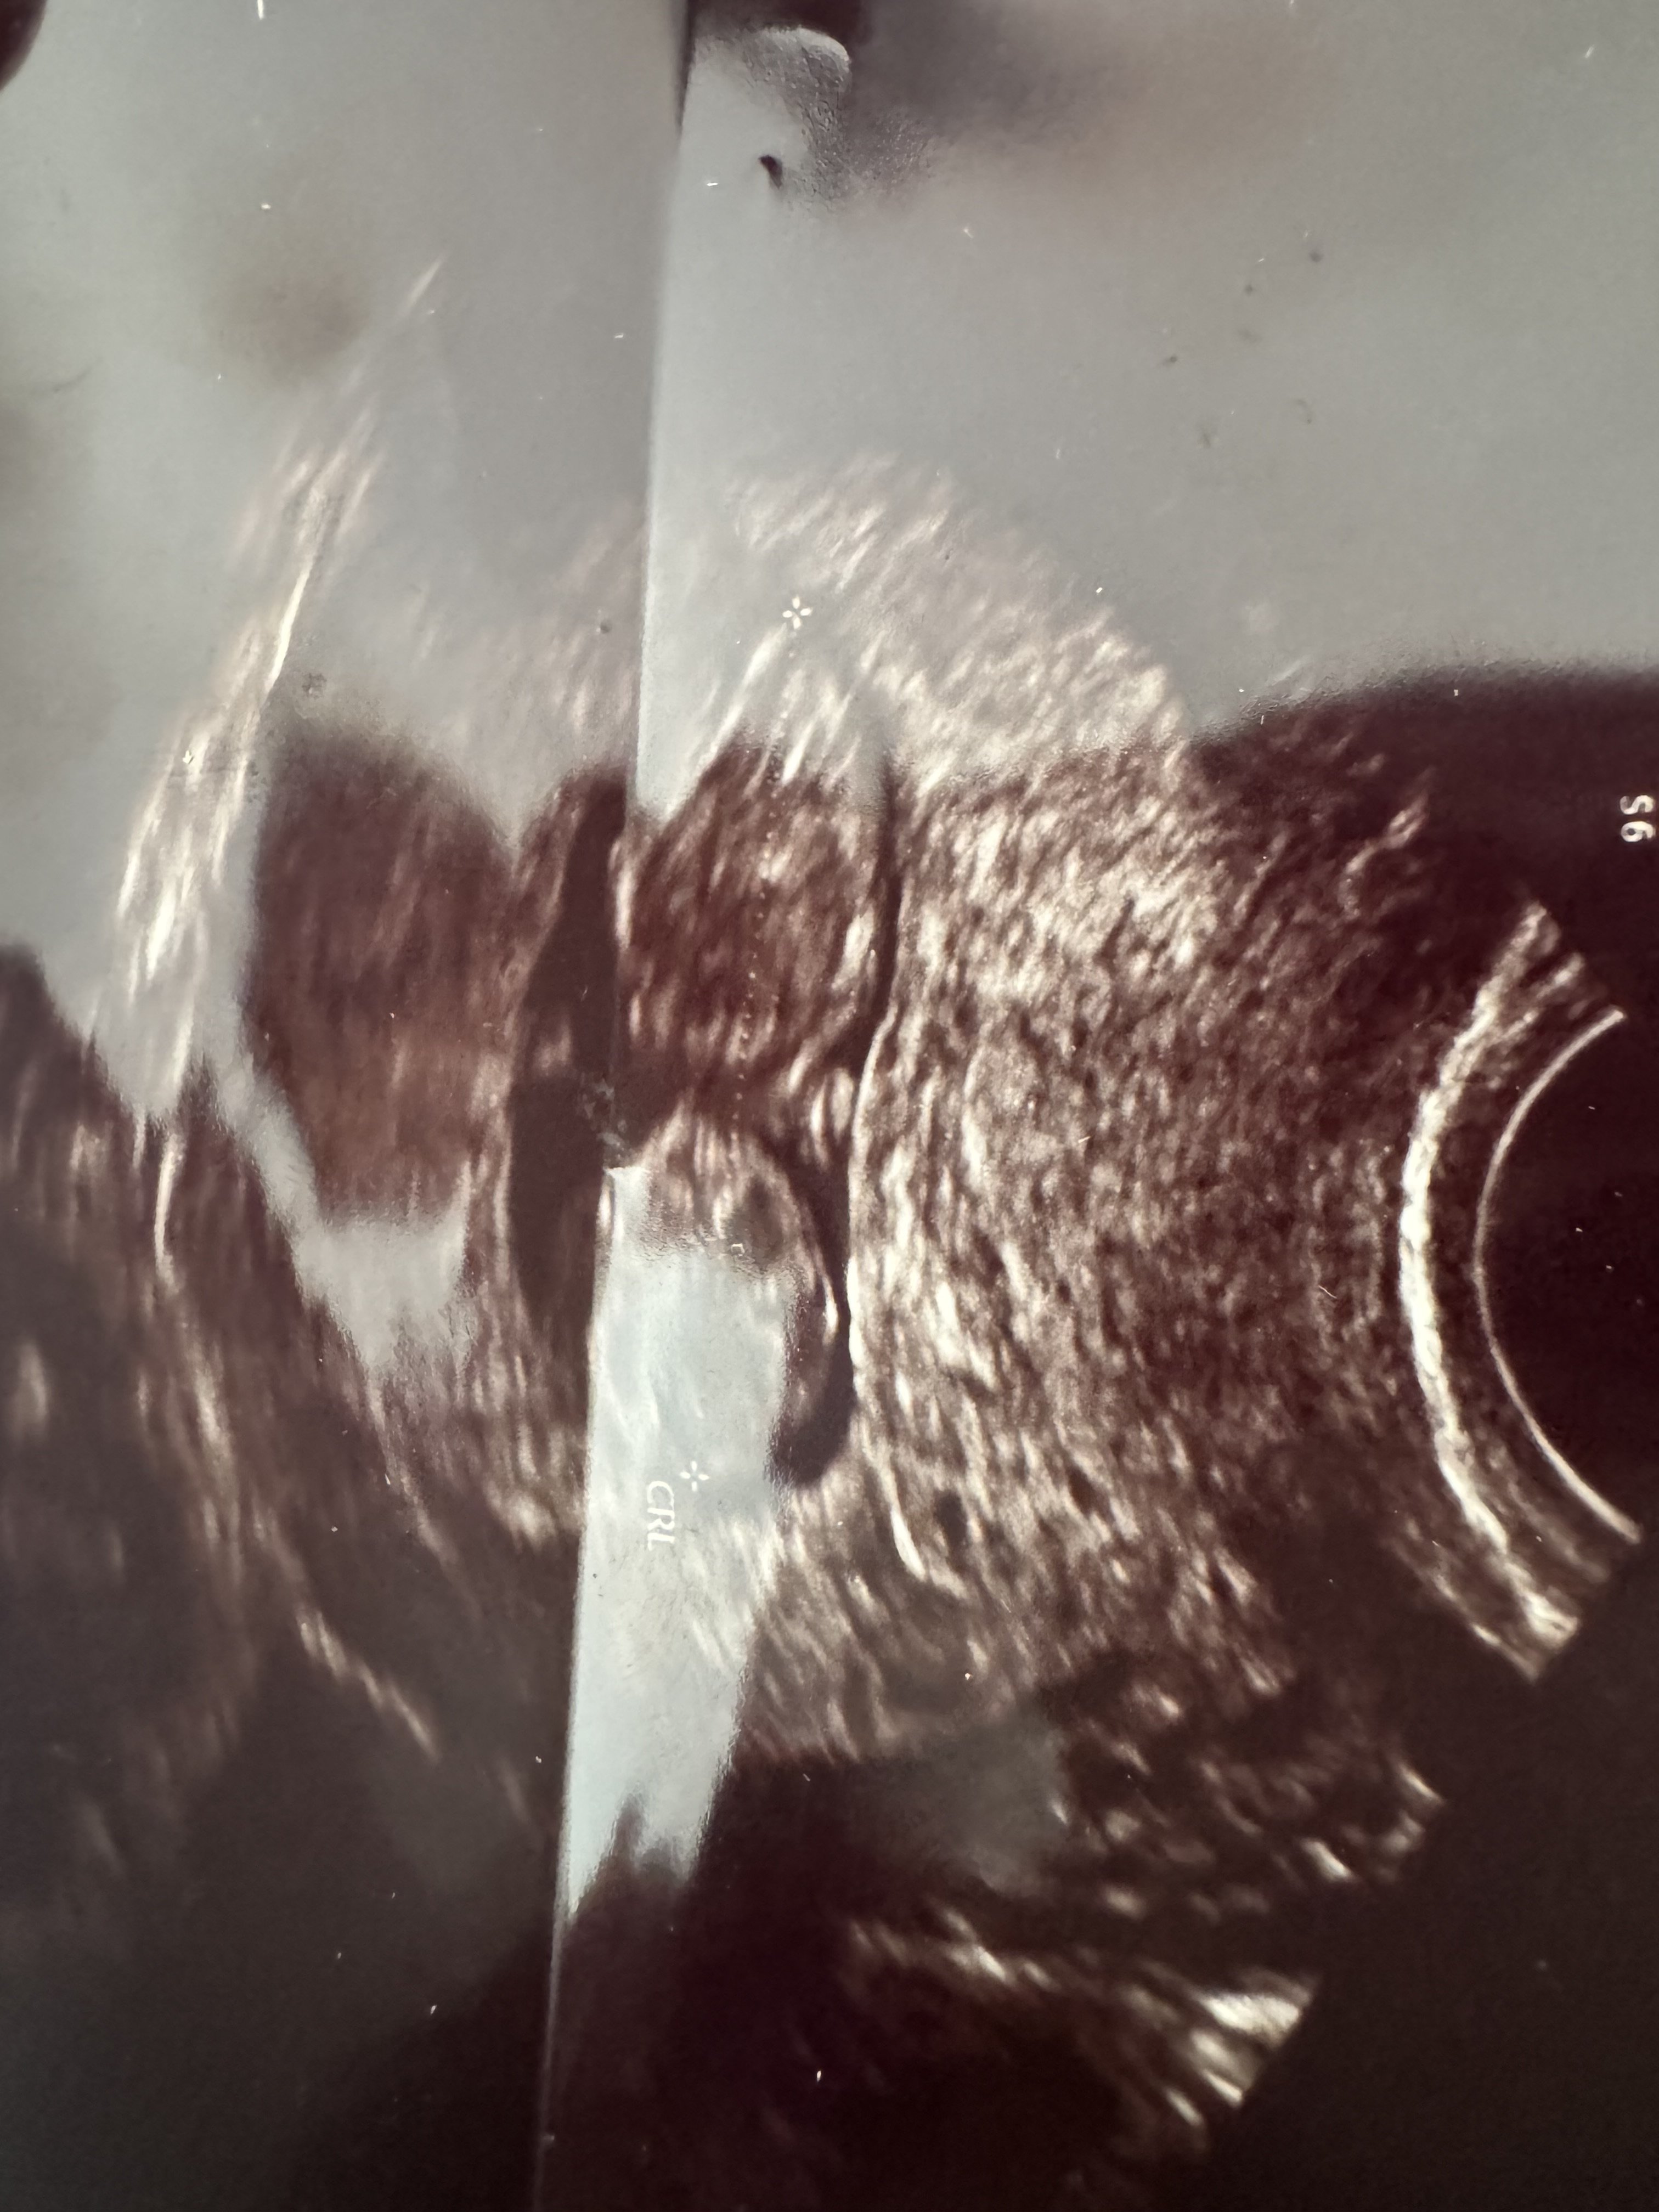

Jestem w 11 tyg zaraz wchodzę w 12 tydzień czekam za prenatalnymi we wtorek ogólnie od początku ciąży słyszę jakieś problemy normy i sam stres . Lekarka moja stwierdziła że nie ma wód płodnych dziecko się dusi i ma nadzieję że dotrwam do prenatalnych bo sama jest ciekawa co tam wyjdzie . 3 h później pojechałam za namową lekarza innego po konsultacji telefonicznej na izbę przyjęć we Wrocławiu gdzie Pani doktor dokładnie mnie zbadała i powiedziała że wody są dziecko ma miejsce żeby się ruszać co nawet zaobserwowałyśmy na ekranie że się rozpycha faktycznie stwierdziła że wód mogło by być więcej ale mówiła też że na tak wczesnym etapie jest wszystko malutkie że te wody jeszcze mogą nająć bo one będą nachodzić całą ciążę i raz może być ich więcej raz mniej bo dzidzia też rośnie . Kazala spokojnie czekać do prenatalnych i pić 2-3 l wody dziennie . Bardzo się denerwuje bo w sumie to jest nasz mały cud po wielu latach starań i nie udanych ifv nie wiem co myśleć . Dołączam zdj USG z 1 i 2 gabinetu widać różnicę odrazu

• IMG_5650.jpeg

IMG_5650.jpeg

1,1 MB · Wyświetleń: 180

Wiesz co na tych zdjęciach jest inny kąt w ogóle i na pierwszym pęcherzyk jest przez to zakrzywiony. Po prenatalnych będziesz wiedziała jak oblicza ile masz dokładnie wód. Na tą chwilę nic więcej nie można powiedzieć. Postaraj się nie myśleć o tym i nie denerwować, bo to może zaszkodzić bardziej. Wtorek już tuż tuż. Trzymaj się!